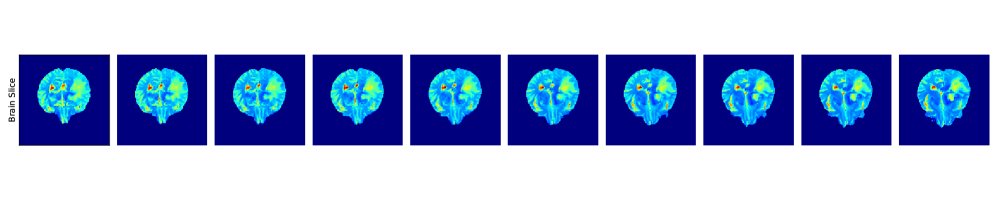

Our objective is to perform brain tumor segmentation on the BraTS2020 dataset [30]. This dataset contains 3D brain MRI volumes. The data is divided into two categories: (1) High-grade gliomas (HGG), (2) Low-grade gliomas (LGG). Each brain scan is accompanied by a simplified segmentation mask defined as 0: non-tumor tissue pixels and 1: tumor tissue pixels. We train our segmentation model using brain scans with HGG tumors, from which we select 190 for training, 10 for validation, and 10 for testing. During training, we apply a range of augmentation techniques. We refer to SI B.6 for further details on the datasets and employed augmentation techniques; we also include an ablation on the noise corruption technique.

Our evaluation is conducted on 10 held-out HGG brains and an additional set of 10 LGG brains. For the HGG cases, we evaluate the model not only on FLAIR MRI scans, which were used during training, but also on T2T_{2}-weighted scans, representing a different MRI modality. For the LGG cases, performance is assessed on both axial (z-axis) slices, aligned with the training direction, and x-axis slices, offering a side view of the brain and allowing us to test the model’s generalization to previously unseen anatomical orientations.

SI B.6, Fig. 34 shows the relation between relative L1L_{1} segmentation error and our likelihood certificate across four test scenarios. Most low-error cases are correctly classified as ID, while nearly all high-error cases (relative L11.0L_{1}\geq 1.0) are identified as OOD. Furthermore, it is crucial to highlight that our approach effectively identifies OOD samples originating from a different MRI modality, namely T2T_{2} MRI scans (see subfigure 3 in Figure 34).

Aggregating all datasets, the 2d histogram of error vs. likelihood (SI B.6, Fig. 35(left)) shows high density around low likelihood and errors near 1.01.0, i.e., OOD. Low-error points cluster near the threshold but remain ID. The log-likelihood histogram (middle) is right-skewed, favoring higher values. Finally, error histograms (right) confirm that ID samples are mostly low-error, while OOD samples are dominated by high-error cases, with some low-error outliers.